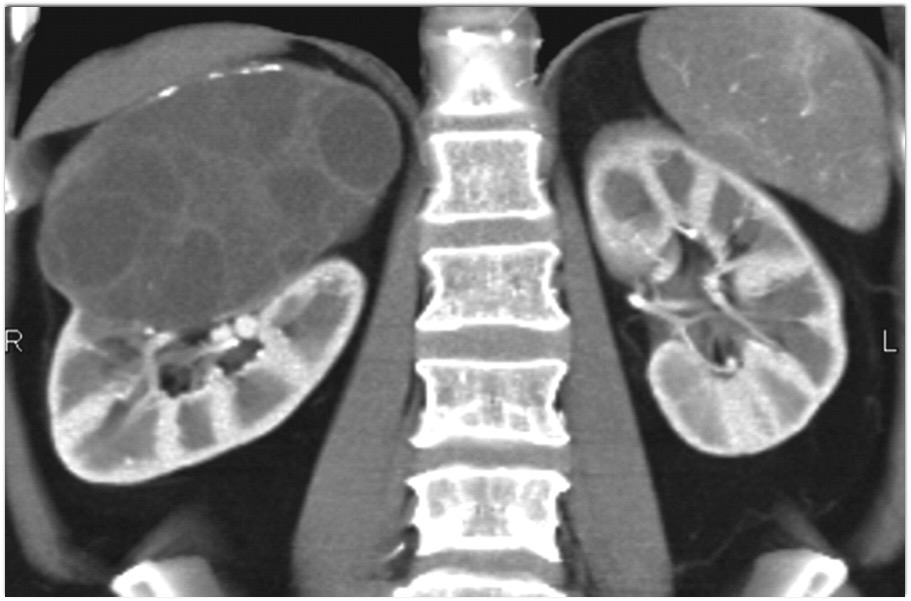

9) The best diagnosis in this 30ish year old female is?

renal cell carcinoma

MEST tumor (mixed epithelial and stromal tumor)

Wilms tumor

polycystic kidney disease